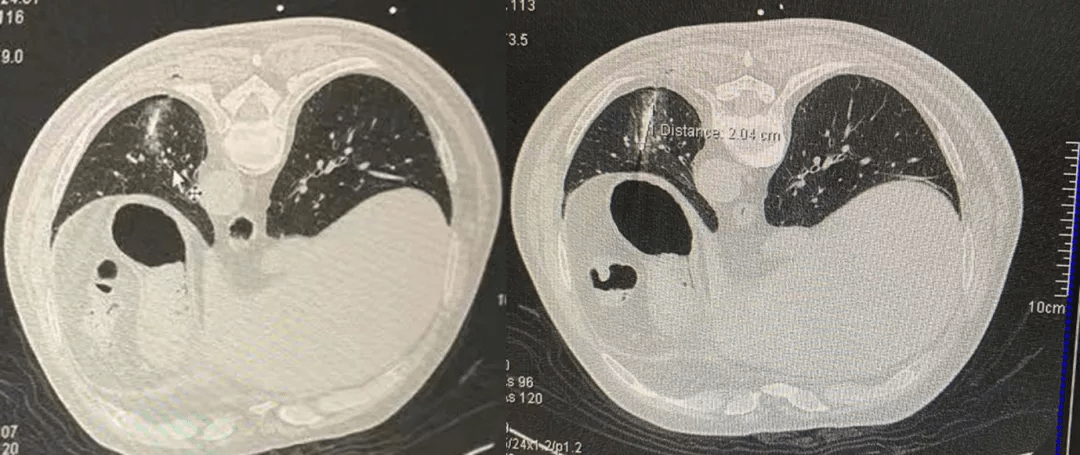

上图:左肺下叶后基底段肿瘤消融术中

上图:CT扫描确认(左),消融后CT扫描影像(右)